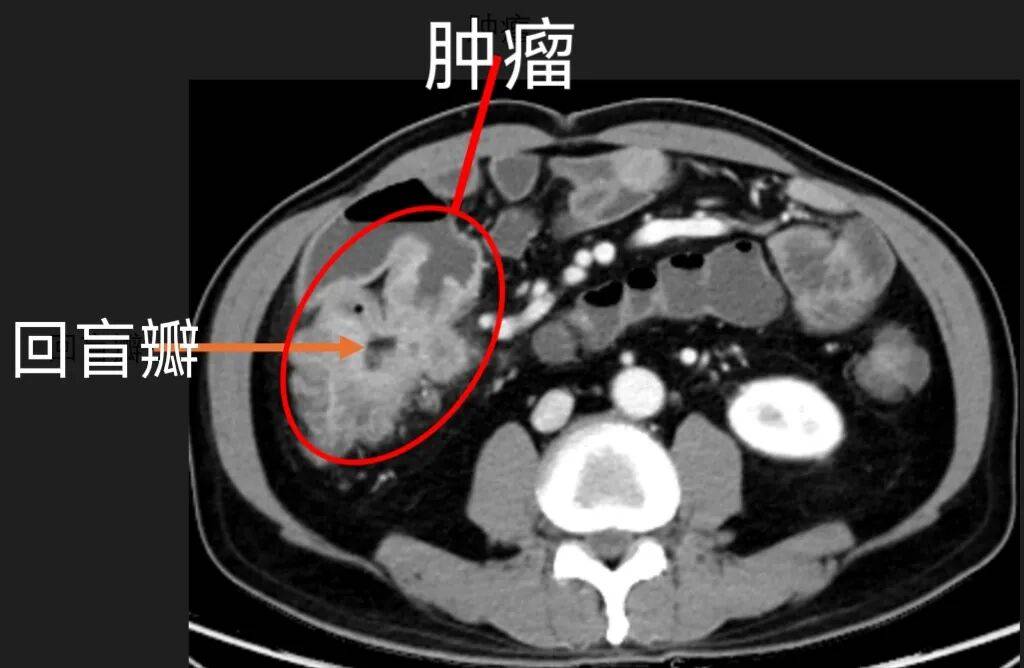

可张先生不知道,此时瑞金医院有人早已为他的病情捏了一把汗。放射诊断科赵雪松副主任医师凭借多年专注小肠疾病的丰富经验和细致观察,在张先生的小肠CT薄层重建影像上,敏锐发现了关键隐患:这是一个巨大的病灶,病灶长在回盲部,回盲瓣变形了,这种位置的病变很容易被误诊为普通炎症。更让人担忧的是,影像上肠壁的僵硬感、不均匀强化、周围淋巴结肿大,都指向了恶性肿瘤的可能。

各项术前准备就绪后,在麻醉科、手术室团队的通力配合下,赵任主任医师与团队张弢,景晓乾,陈子龙医生,共同为患者实施腹腔镜微创手术。术中探查发现,患者腹腔有轻度粘连,5*4cm 大小的肿瘤位于回盲瓣的小肠侧,已侵犯肠壁外层,且与十二指肠紧密相邻,手术需格外精细精准。凭借精湛医术,赵任医生带领团队行云流水般完成肿块切除,同时完整保留了患者的重要脏器功能。术后病理确诊为“弥漫性大B细胞淋巴瘤”,幸运的是,周围24枚淋巴结都没有发现肿瘤转移,手术达到了根治效果。